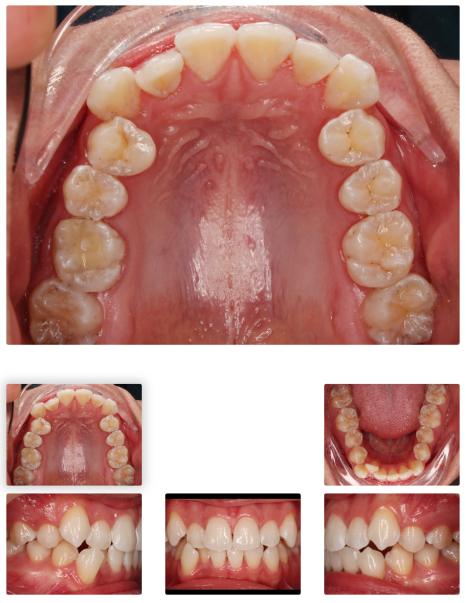

< 인비절라인 돌출입 교정 사례 중 일부>

김병*님 치료기간: 23.1.17 - 24.12.07 (약 2년)